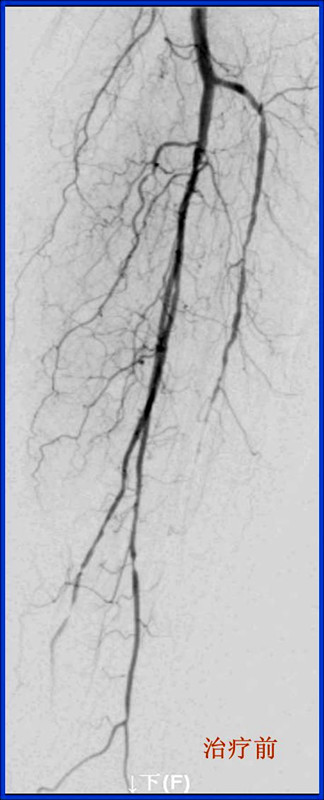

8月26日下午,我院中医外科叶海东医生和心内科潘兴丰医生合作,在放射科和手术室人员的协助配合下,成功完成了2例下肢动脉造影+球囊扩张术。据悉,这是我院首次完成血管腔内介入手术。